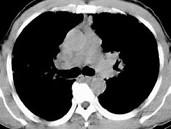

问题 男,38岁,咳嗽,咳痰,关节疼痛,外周淋巴结肿大,结合CT图像,最可能的诊断是 ( )

选项 A.肺泡蛋白沉积症 B.肺间质病 C.结节病 D.肺结核 E.霍奇金病

答案 C